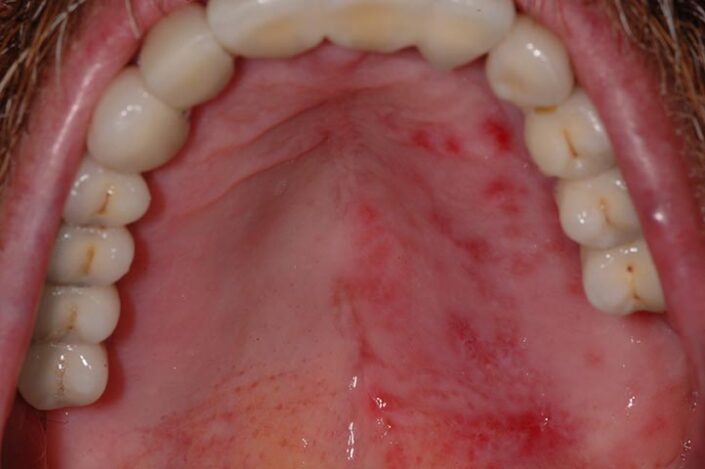

La si distingue facilmente dalla stomatite aftosa poichè interessa la quasi interezza della bocca associandosi a febbre fino a 40 gradi, nausea, gonfiore delle gengive brividi cefalee linfonidi ingrossati dolore e bruciore molto più forti e maggior numero di lesioni (vescicole a grappolo o lesioni tondeggianti di maggior dimensione contenenti un liquido sieroso limpido che una volte rotte portano ad ulcerazioni superficiali)sia sulla lingua sia sulla gengiva sia sul palato sulle labbra e sulla mucosa delle guance